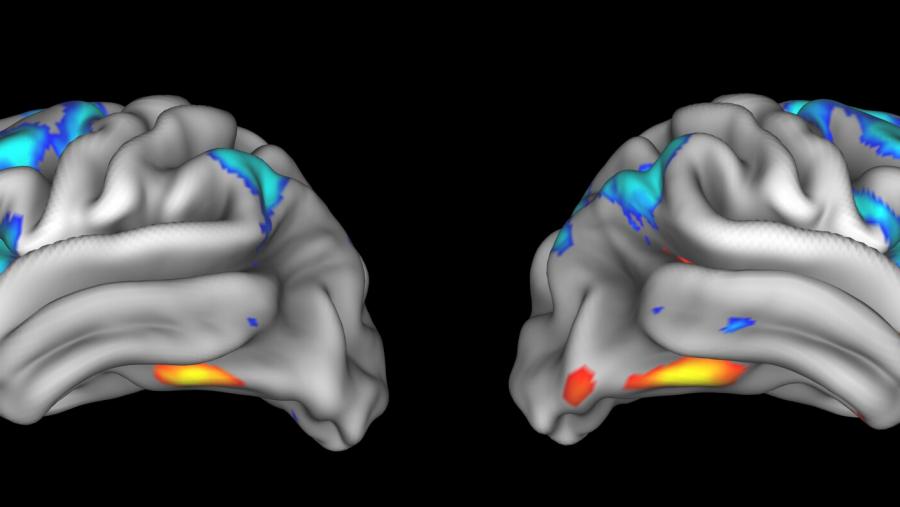

Treating the brain with non-invasive stimulation

Published: April 26, 2023

Topics:

Small Business Programs

Can resetting brain circuits help people find recovery?

Published: November 15, 2022

Topics:

Drug Development